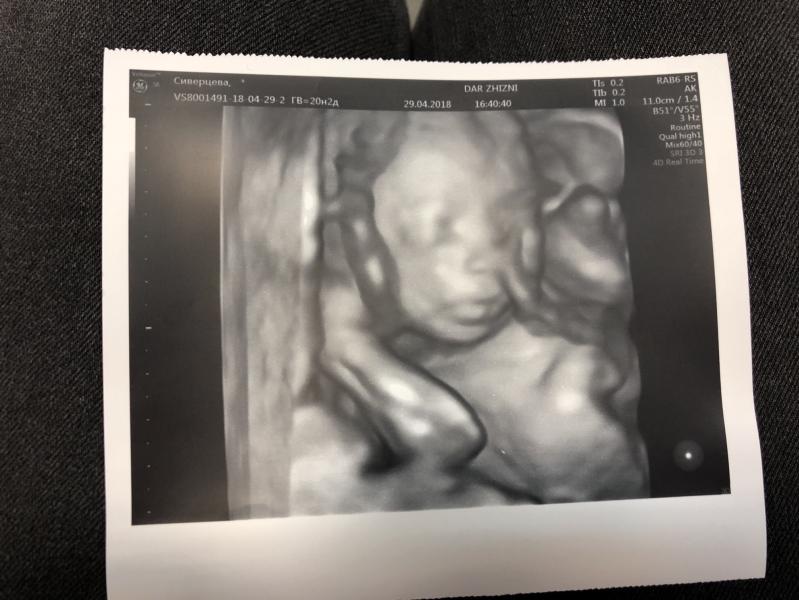

Второй скрининг пройден 🙏🏻💜

Раньше меня пугали 3D снимки УЗИ, а на своего котика смотрю и прям умиляюсь 😊

@rus14, да, на 3D прям лицо) а на обычном узи, все-таки очертания скорее

На 3D все лучше видно, верно? Я на скрининг ездила было обычное УЗИ, а на 23 запись на 3D